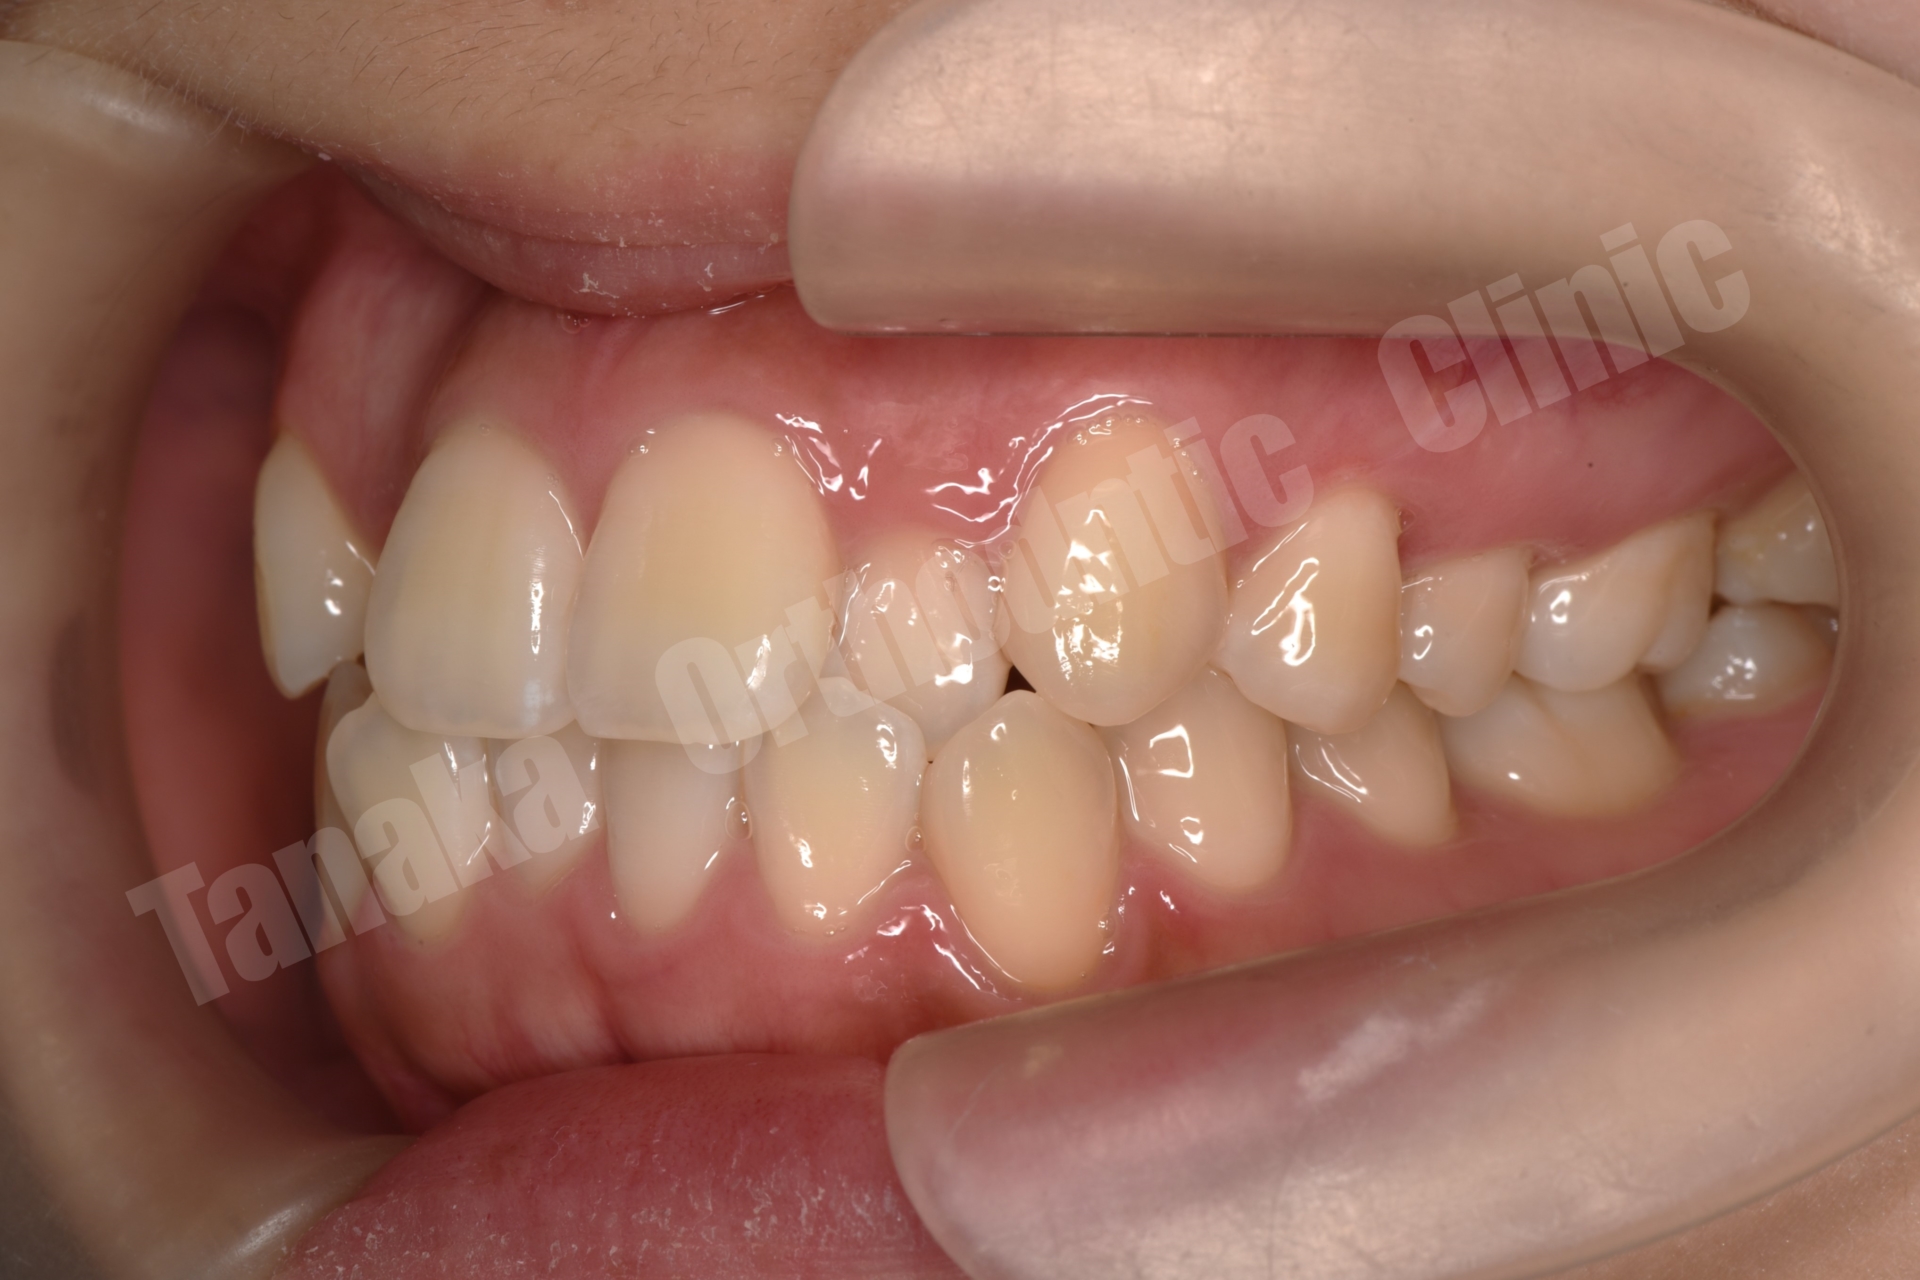

| 主訴 | 上下顎前歯のがたがた、口元が気になる |

| 年齢・性別 | 10代、女性 |

| 診断 | 上顎前突傾向(下顎骨の後方位)、上下顎歯列の叢生、上下左右8番を認める |

Angle Class I(第一大臼歯の正常なかみ合わせ)

ハイアングル傾向(下顎骨が後下方へ回転するタイプ)

上下前歯部に叢生(がたがた歯列)

下顎前歯(L1)が前方に傾く「唇側傾斜」